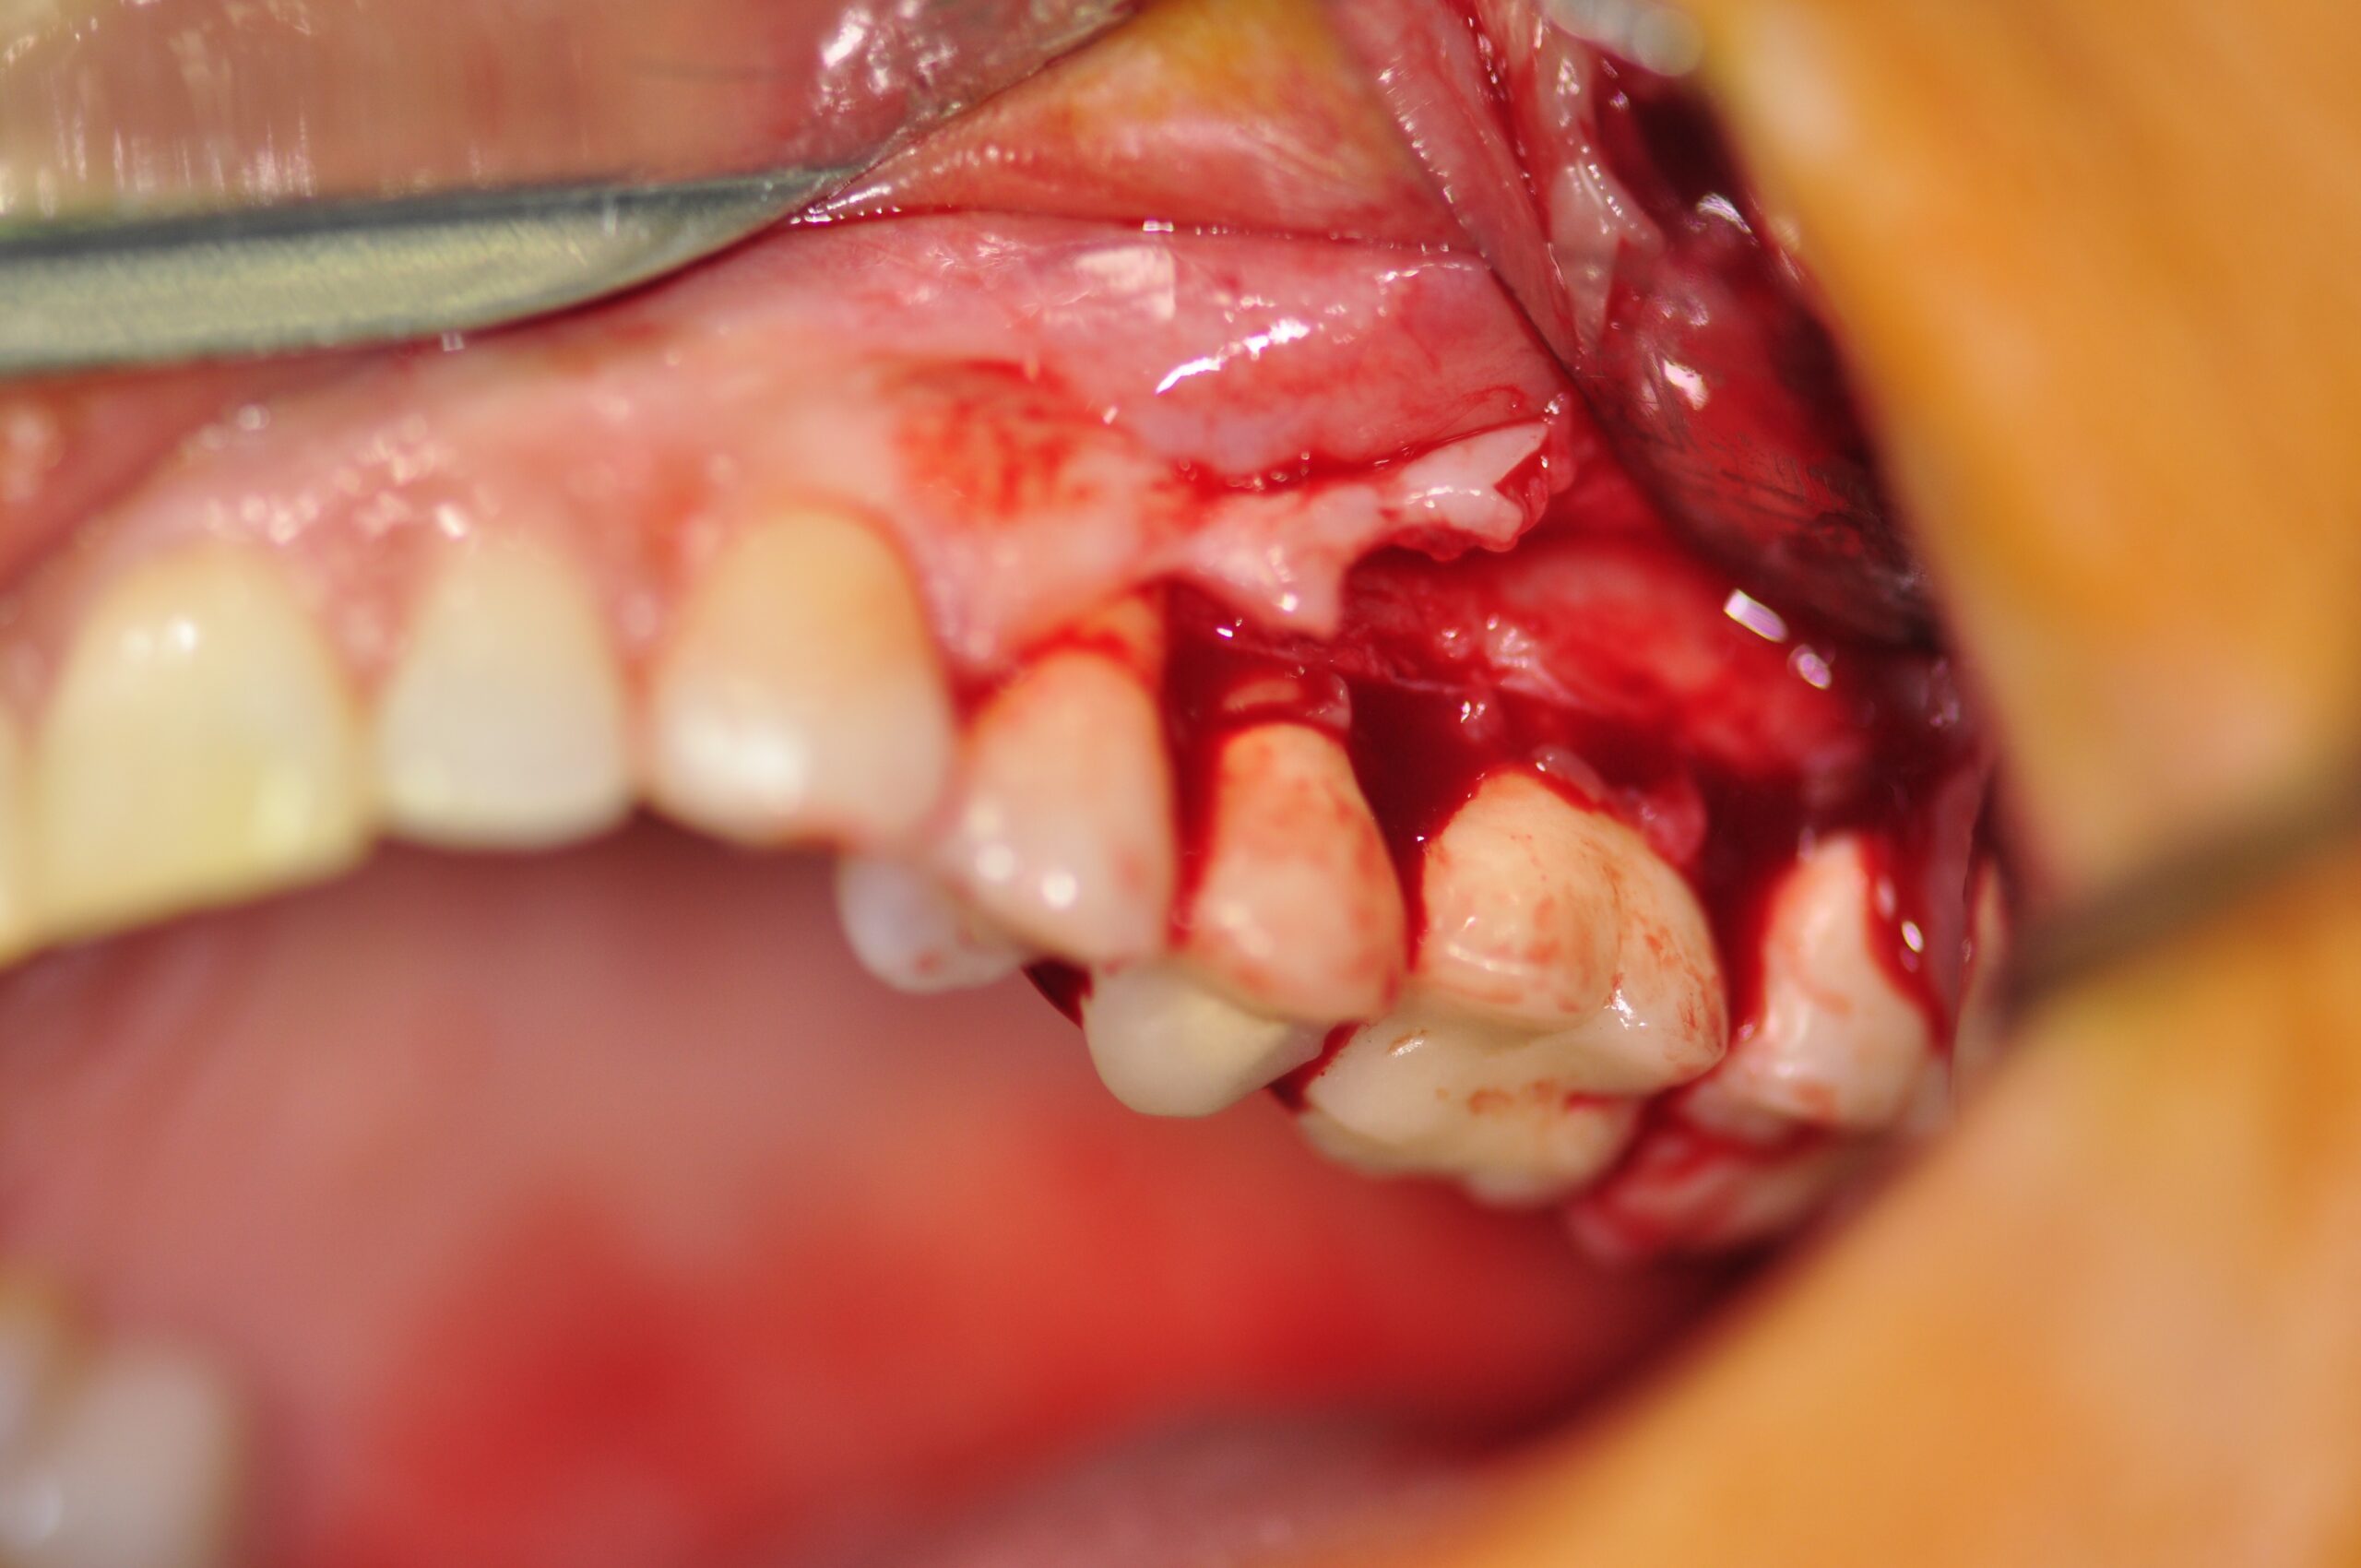

Celles-ci incluent la chirurgie à lambeaux pour un nettoyage en profondeur, la greffe gingivale ou conjonctive afin de renforcer les tissus, et la chirurgie du sourire gingival (ou "Gummy Smile") pour réharmoniser l’esthétique du sourire.

- Chirurgie à lambeaux